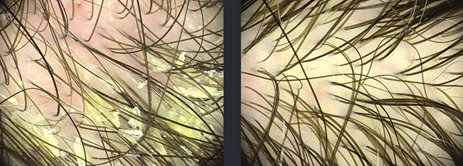

OBRAZ TRICHOSKOPOWY